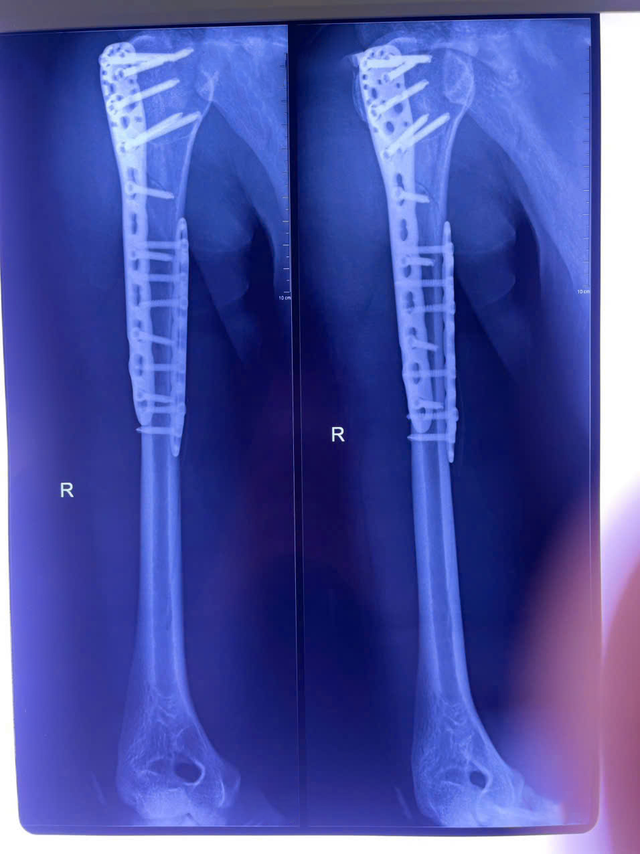

Suốt gần 3 giờ căng thẳng, ê-kíp khoa Chấn thương chỉnh hình đã thực hiện thành công ca phẫu thuật. Ổ gãy được xử lý triệt để: Rửa sạch, loại bỏ máu tụ, nắn chỉnh và cố định bằng nẹp titan cùng vít khóa. Dưới sự hỗ trợ của hệ thống C-arm hiện đại, cấu trúc xương tại vị trí tổn thương được cố định vững chắc và các đầu vít không ảnh hưởng đến mặt khớp.

Sau phẫu thuật, vị trí gãy xương cánh tay được cố định vững chắc.

Ảnh: BVCC